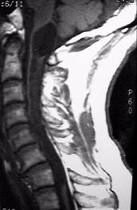

脊髓外傷症狀,體徵和診斷

急性的脊髓橫貫性損害立即引起受損水平以下鬆弛性癱以及所有感覺功能與反射活動(包括自主神經功能活動)的喪失(即所謂脊髓休克).在數小時或數天之內,鬆弛性癱瘓逐步轉為強直性截癱,這是由於下行抑制消除故而正常肌腱牽伸反射出現亢進.以後,如果腰骶段脊髓功能完整無損,可出現屈肌痙攣,而深腱反射與自主神經反射也有恢復.

脊髓的不完全性損害引起部分性運動與感覺功能的喪失.隨意運動出現障礙.感覺障礙的具體表現根據受損的傳導束而定:如後柱受損可引起位置覺,振動覺以及輕觸覺的喪失;如脊髓丘腦束受損,則出現痛覺,溫度覺以及往往還有輕觸覺或重觸覺的喪失.脊髓半橫斷性損害引起同側下肢的強直性癱瘓伴深感覺的喪失,以及對側下肢的痛覺與溫度覺喪失(Brown-Sequard綜合徵).脊髓損害的水平可以根據臨床線索來判定.